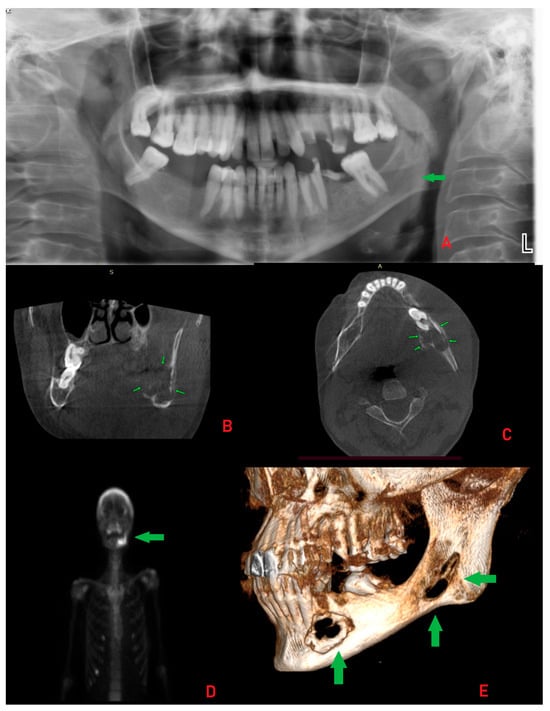

The following figure is a comparable case image to the presented case; however, the BT lesions found were not that advanced locally and were misdiagnosed as other minor jaw lesions. However, the performance of SPECT-MiBi improved greatly on the final diagnosis. The occurrence of BT is a very troublesome disease in identification in some atypical cases, especially in small lesions, without significant aggressive bone loss, extracortical spread, and when they have a similar appearance to a normal jaw cyst [8,9]. The differential diagnostics might be difficult, when some bone lesions in jaw bones can mimic a vast scope of other tumors and lesions of both benign and malignant origins ((A,B) with blue-orange and purple-orange orientation lines). Sometimes, regardless of a full blood-work and evaluation of calcium-phosphatase markers, very good radiology, the full scope of the disease might often be camouflaged by other general patient co-morbidities. In cases of any doubts, a special scintigraphy of the parathyroid glands (SPECT-MiBi) (Black arrows, (C,D)) is very important, along with a biopsy to fully confirm this disease [2,4,8]. The scope of BT in PHP/SHP might have many levels of bone changes, blood serum markers exhibition, and, therefore, histopathology. Acquiring more valuable material for accurate histopathology is quite important. The following factors may be associated with various bone changes, the spectrum of lesions, and osteolytic processes detected within a single biopsy specimen. BT can manifest in various ways and with different possible radiological appearances, which are greatly dependent on the scope, intensity, and duration of PHP/SHP [4,5,6,7]. The scope of the surgical approach towards the parathyroid glands and thyroids, if necessary, should be discussed among endocrinologists and general surgeons after a careful individual examination of each case. Collectively, these reports highlight that BT of the jaws is diagnostically challenging due to their overlap with odontogenic and malignant lesions. Accurate diagnosis requires correlation of imaging with biochemical and histopathological findings, and surgical excision may be necessary when systemic therapy proves insufficient.